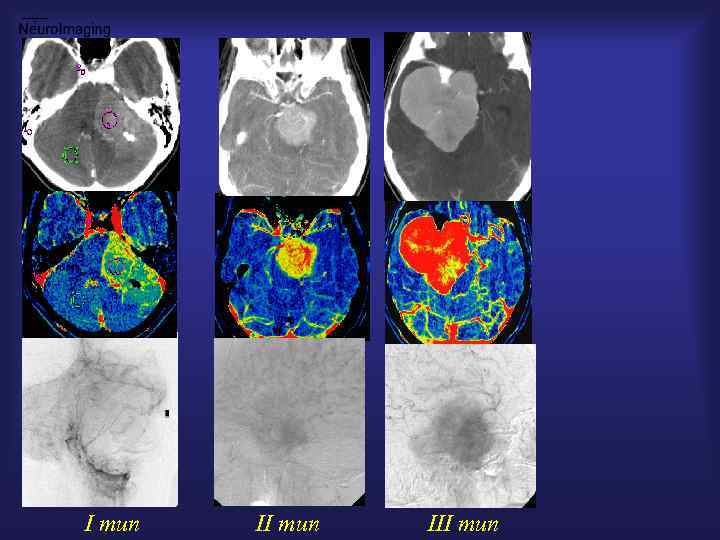

Менингиома ( МРТ/ СКТ - перфузия, ангиография) От анатомии К физиологии

I тип III тип

Множественные менингиомы - СКТ 10 сек. CBV Перфузия 20 сек. 30 сек. CBF